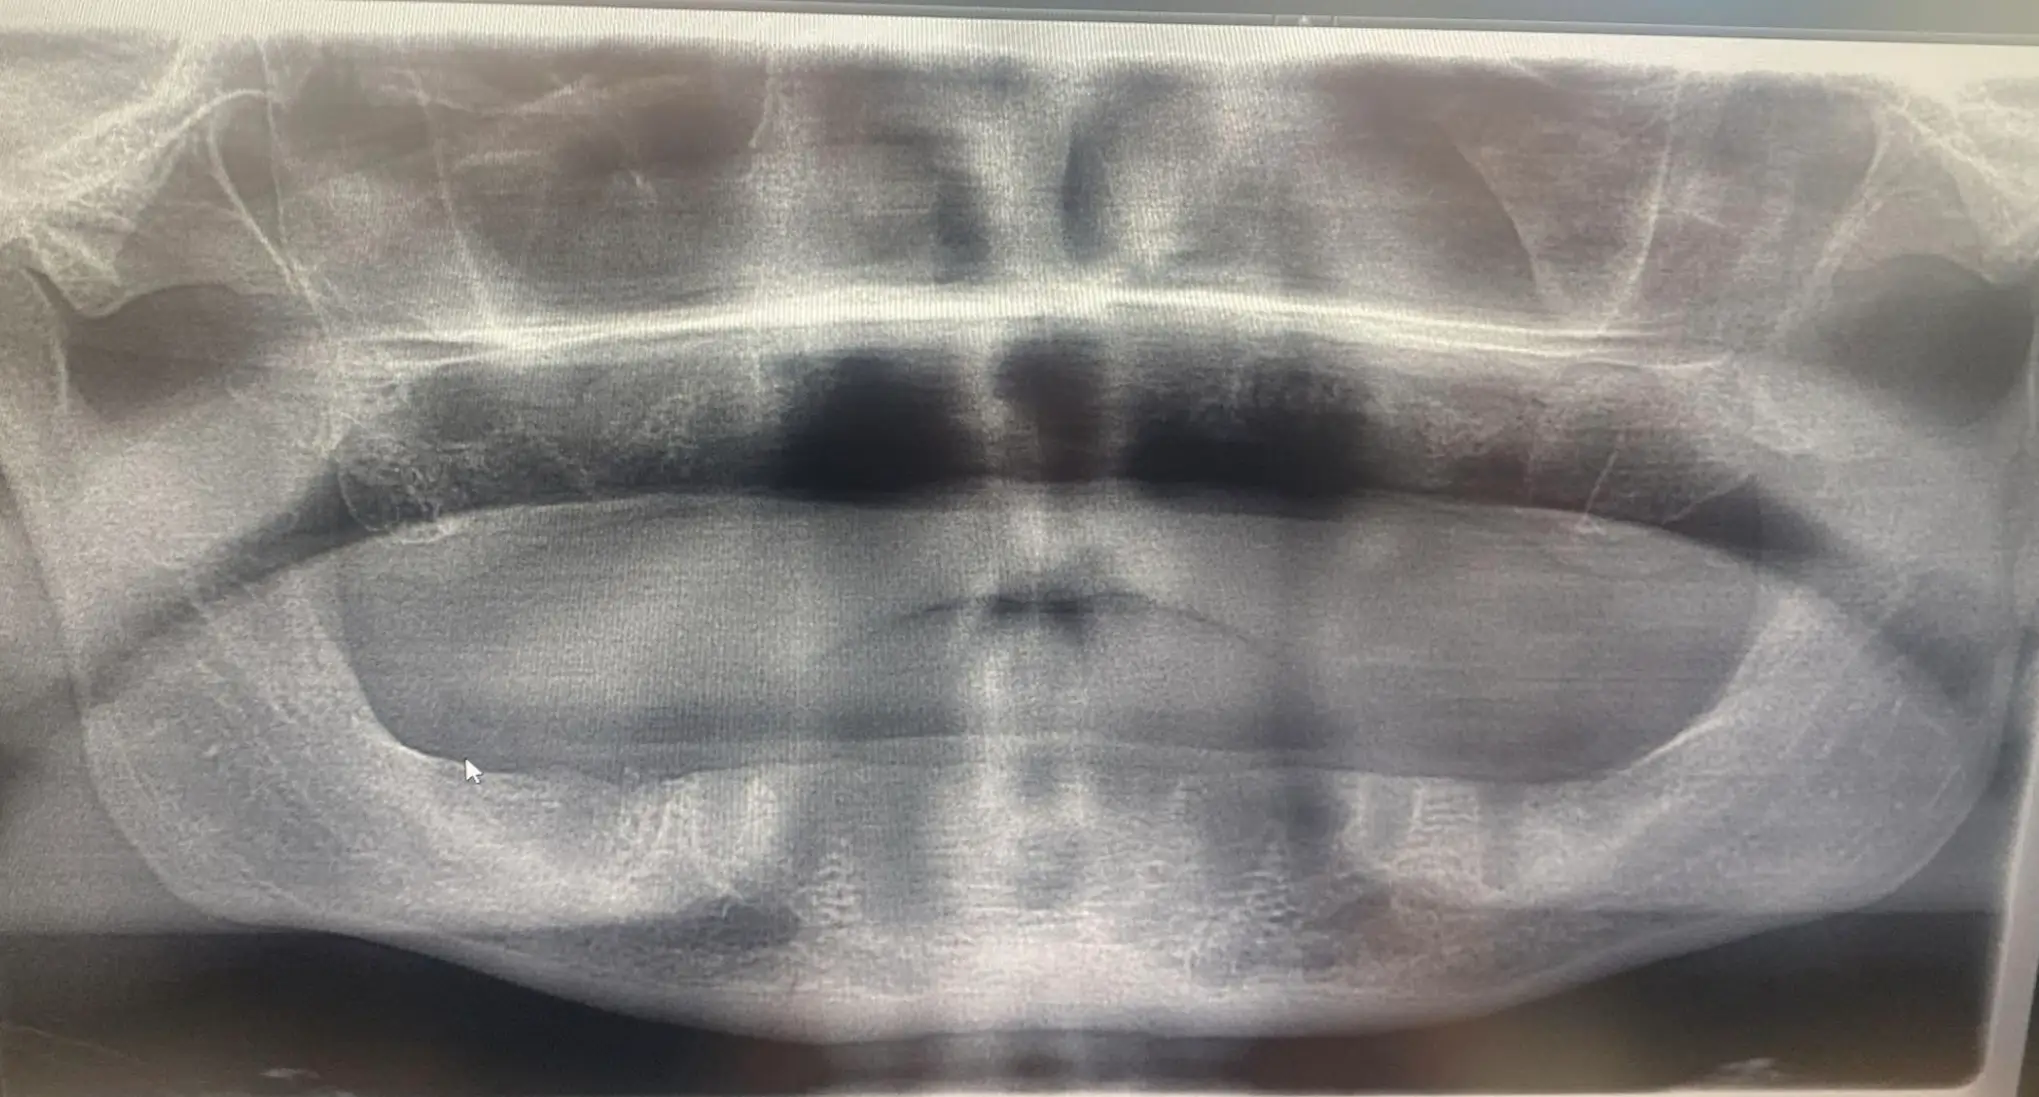

The GoFundMe goes on to say that UK dentists have since informed Jon that he 'did not have sufficient bone to support the implants' and that he has 'no ridge, so dentures are not suitable for him'.